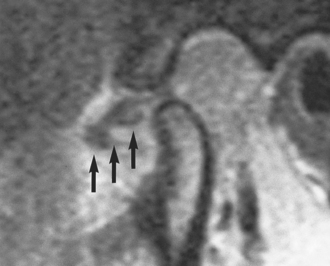

Many anatomy texts show the disc within the TMJ to be superior and slightly anterior to the condylar head when the teeth are in occlusion, with the two main ridges of the disc placed one behind and one in front of the condyle (Fig. 16.2). During mouth opening the condyle rotates against the disc and the disc slides forwards and downwards along the articular eminence, but the ridges on the disc remain on either side of the condylar head (Fig. 16.3). This forward slide in the upper joint space is called translation. In general, much of the early part of mouth opening occurs as a hinge movement in the lower joint space and later in opening a greater part of the movement is translatory.

image

Fig. 16.2 (a) MRI of the normal disc/condyle relation, mouth closed. (b) Diagram of the same. AE = articular eminence; AR = anterior ridge of disc; PR = posterior ridge of disc; GF = glenoid fossa; SL = upper lamina of posterior attachment; EAM = external auditory meatus; IL = lower lamina of posterior attachment; CH = condylar head; SPt = superior pterygoid muscle.

Fig. 16.3 (a) MRI of the normal disc/condyle relation, mouth open. (b) Diagram of the same. Abbreviations as defined in the legend to Fig. 16.2.